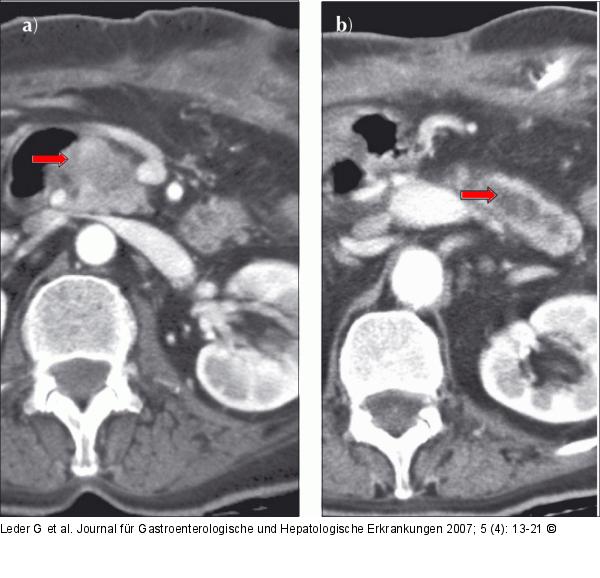

Abbildung 5: Chronische Pankreatitis Die sich erstmals darstellende hypodense Raumforderung (→) im Pankreaskopf führt zu b) zunehmender Pankreasgangerweiterung (→) im Korpus/Schwanz (CT 13.9.05). |